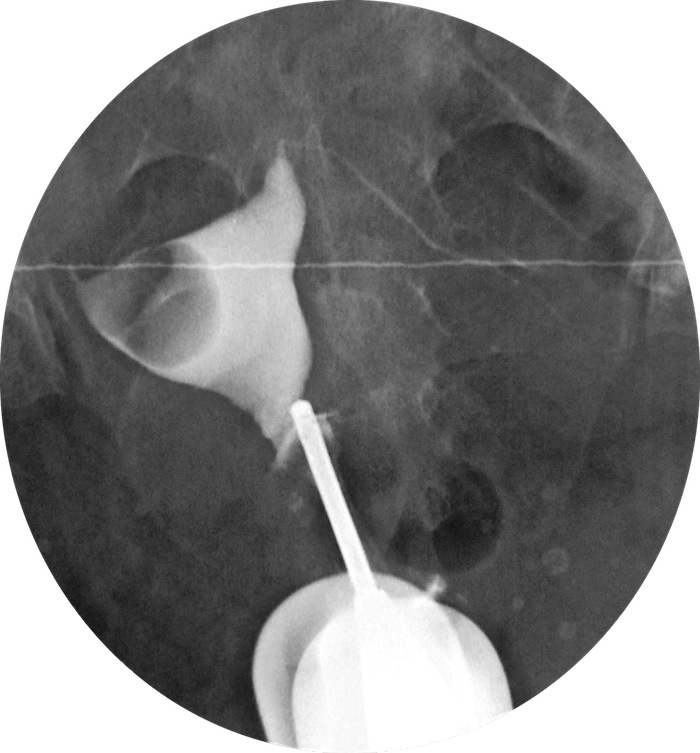

Гистеросальпингография: описание и фотографии